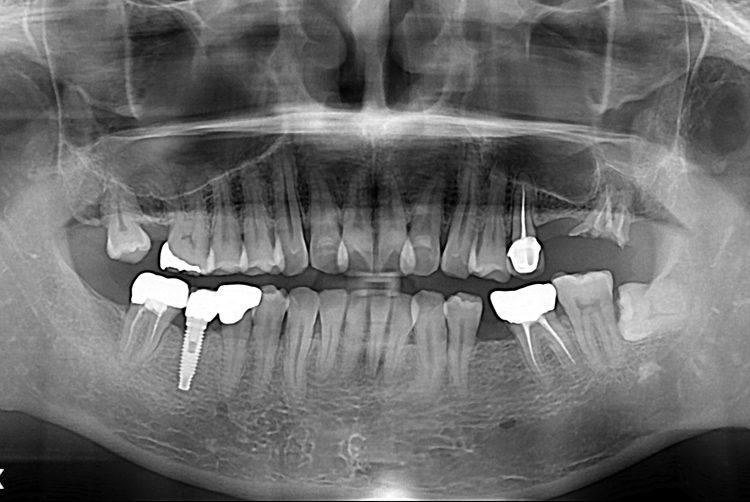

[임플란트] 어금니 임플란트

치료전 : 2017-07-19